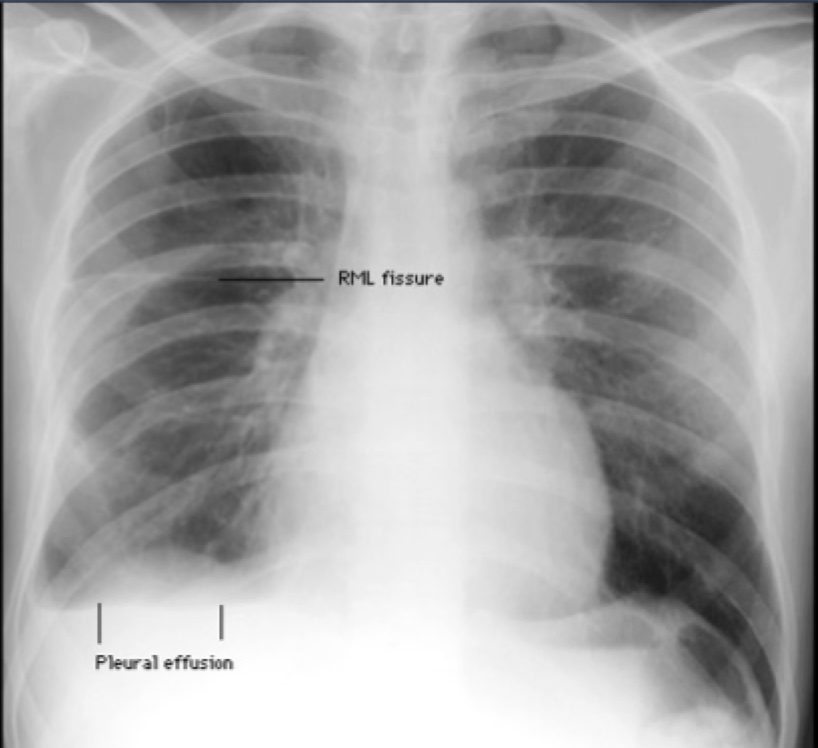

Pleural effusion

-must have 75–200 mL to be visible in costophrenic angle

-May appear loculated (~mass/pseudotumor) if there are pleural adhesions

-Round/oval fluid collections in fissures resembling intraparenchymal masses (pseudotumors)